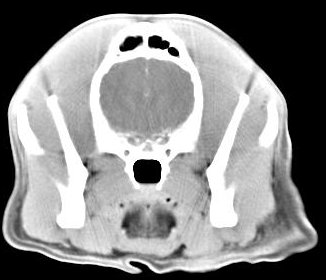

imágenes de TC en el perro | ||||||||||

ejemplo de imágenes de TC en el perro. Nótese la celulitis en la región parotídea izquierda | ||||||||||